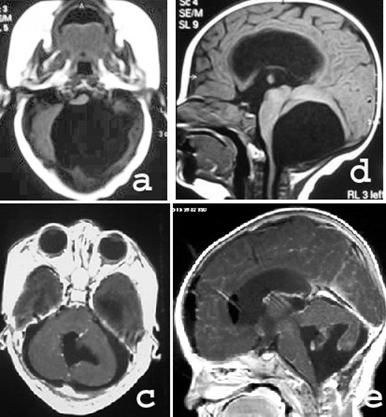

Resim 11: (a) BT’lerde ve

(b) dikey MRG kesitlerinde beyincik arkasında yerleşim gösteren araknoid kist.

Resim 12: (a ve

b) yatay ve dikey MRG kesitlerinde dördüncü karıncığı dolduran araknoid kistin ameliyat öncesi görüntüleri.

(c ve

d) aynı hastanın mikroskop ile kistinin çıkarılmasından sonraki görüntüleri.